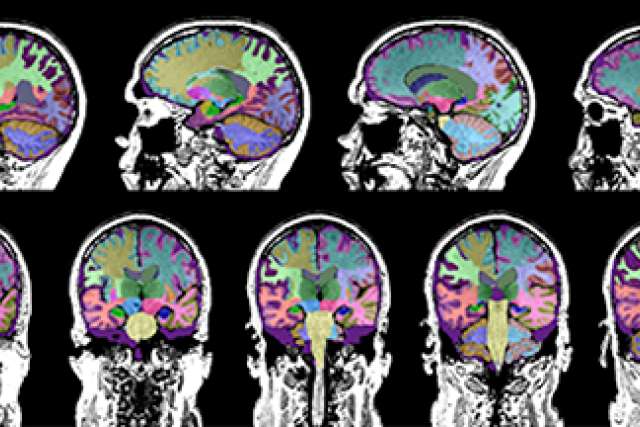

Brain scans for dementia study

Using a software program, UCLA Health researchers were able to measure the volume of different regions of the brain, identifying areas where shrinkage may have occurred.